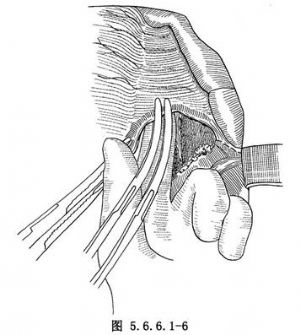

(3)游离胃:探查腹腔,如腹内无明显转移,在胃体上2/3与1/3交界处的小弯侧将胃肝韧带切开,再由相对应的胃大弯侧切开胃结肠韧带,用一条纱带越过胃后将胃向上牵引(图5.6.6.1-4)。继续切开胃结肠韧带,保留胃网膜右动脉,将韧带中的血管钳夹后切断结扎(图5.6.6.1-5)。切开胃脾韧带,切断结扎胃短动脉分支。在暴露术野时注意牵拉脾脏不能用力过大,以免撕裂脾脏(图5.6.6.1-6)。胃大弯侧游离足够以后,离断胃肝韧带,保留胃右动脉(图5.6.6.1-7)。在贲门下方附近的小弯侧摸到搏动的胃左动脉,用3把止血钳夹住,近侧两把,远侧1把,切断后先缝扎一道,再由其深部结扎一道(图5.6.6.1-8),缝扎胃侧血管断端。如此时胃左动脉近侧残端有出血,应先用指压住出血点,再请第一助手以拇指用力按压胸主动脉即可止血,用吸引器将积血迅速清除后,即可从容寻找到出血处予以处理。小弯侧游离完后,在离断贲门之前,请麻醉师将胃管连接在吸引器上持续吸引,将胃内容物尽量吸净,如此可以减少污染并方便吻合操作,吸引完后将胃管向外拔,使其尖端置于贲门上方3~4cm处。用大号直止血钳夹住贲门切断(图5.6.6.1-9)。胃侧断端用中号丝线贯穿缝合,再将浆肌层对拢间断缝合。食管侧断端用贯穿缝合封闭后用阴茎套保护之。将游离完毕的胃提至胸腔。